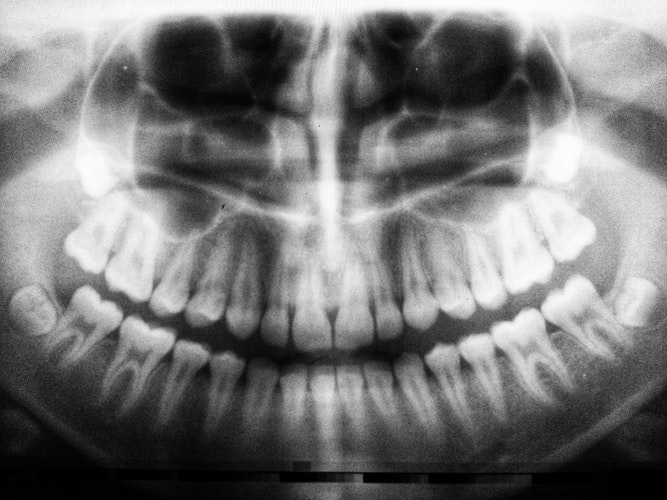

It is a complementary diagnostic examination essential in stomatology in which through it you get to know the entire bone and dental structure.

The patient positions himself in the orthopantomograph, while the X-rays are emitted moving the orthopantomograph around the patient (dental arches). This examination is always done by a radiology technician and may or may not have the intervention of a Physician (Radiologist, Dentist or Stomatologist).